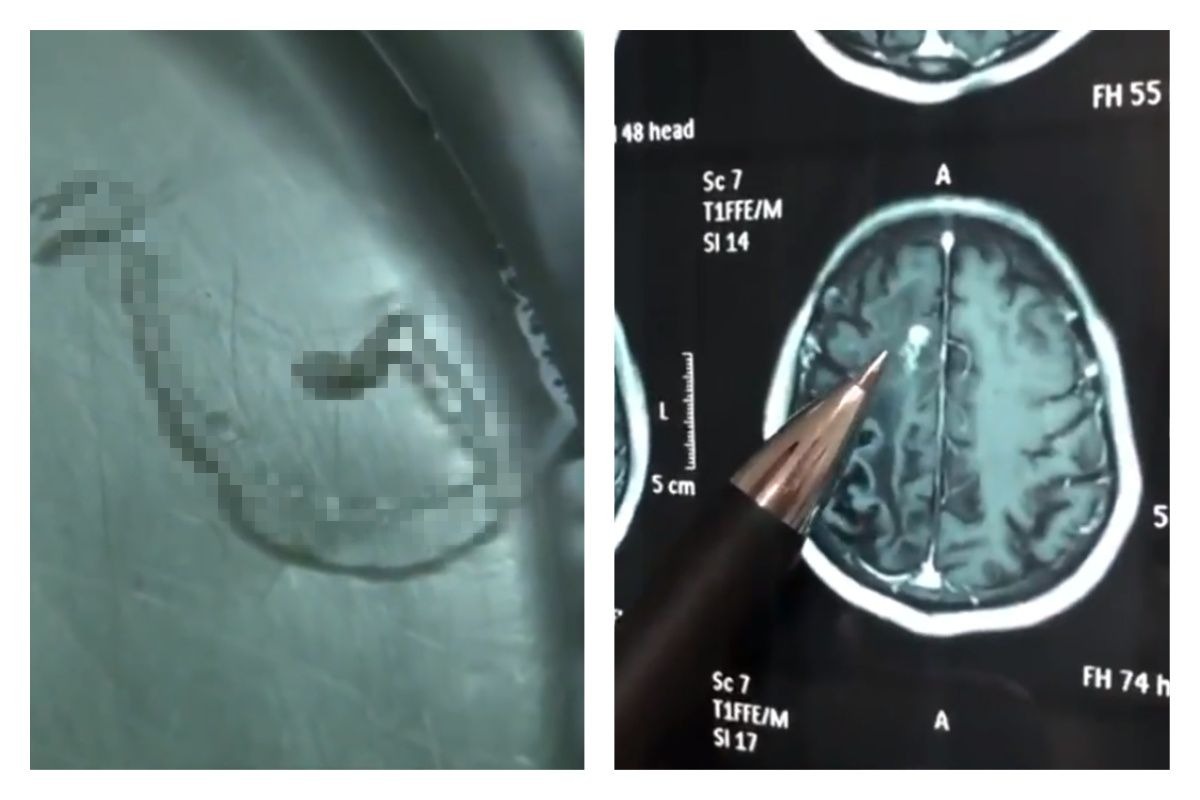

▲男子腦中取出長達 10 公分寄生蟲。(圖/翻攝自梨視頻)

直到最近抽血檢查才發現,男子受到「曼氏裂頭絛蟲」寄生感染。主治醫師閻學強表示,男子腦中的寄生蟲長達 10 公分,恐怕已存活 30 年之久,而男子經過手術,目前已康復。